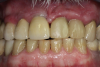

After 4 months of healing and integration of the bone around the implant, the digital workflow was initiated to develop the abutment and treatment plan. Another analog impression was made with an impression post and polyvinyl impression. The laboratory scanned the impression and digitized it to create the emergence profile of the milled titanium abutment and the final restoration (Figure 10 and Figure 11). The patient had a considerably thick soft-tissue profile, allowing a milled titanium abutment. The decision to use a titanium abutment was based on the patient's occlusion and propensity to fracture teeth or restorations. The virtual model was gray because the scanner does not recognize the color of the analog impression. The virtual final abutment and crown were approved and fabrication completed. The final restoration met the patient's esthetic values and his ability to function (Figure 12 and Figure 13).

Fig 12. Six months after cementation.

Figure 12